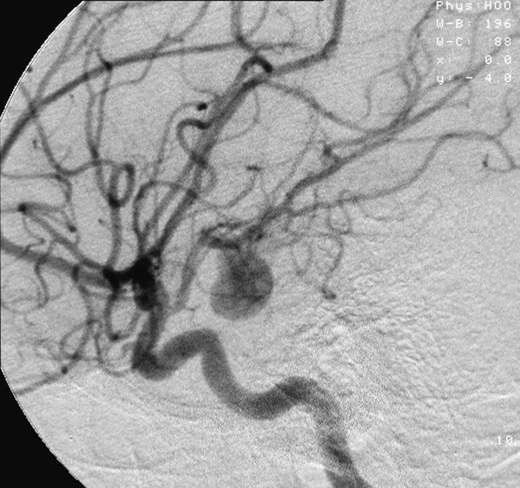

Sau khi chụp chiếu, bác sĩ đã đưa ra kết luận: cô Lee bị mắc chứng bệnh phình động mạch não. Căn bệnh này xuất hiện khá phổ biến ở mọi lứa tuổi, dù người không có tiền sử bệnh án cũng có thể mắc phải.

Cô Lee đau đầu quá mức là do động mạch máu não bị phình căng gây chèn ép các mô não xung quanh. Thấy bác sĩ nói chỉ cần làm phẫu thuật là có thể giải quyết vấn đề, cô và chồng cảm thấy rất an tâm.

Phình mạch não (Aneurysm) là sự phình to của một phần thành mạch máu não tại nơi thành mạch máu bị yếu. Bệnh có thể gây xuất huyết khoang dưới nhện, tụ máu não, tổn thương não, liệt, hôn mê hay tử vong.